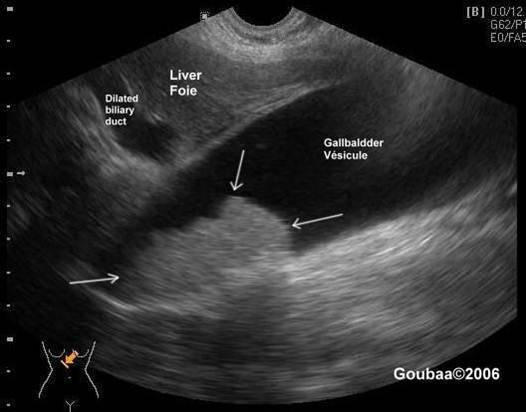

Biliary Obstruction

aka: Double channel

Shot gun

Double barrel

Parallel channel

(dilated biliary duts: A CBD more than 6mm in diameter is considered borderline and more than 10 mm is dilated – will vary by protocol)